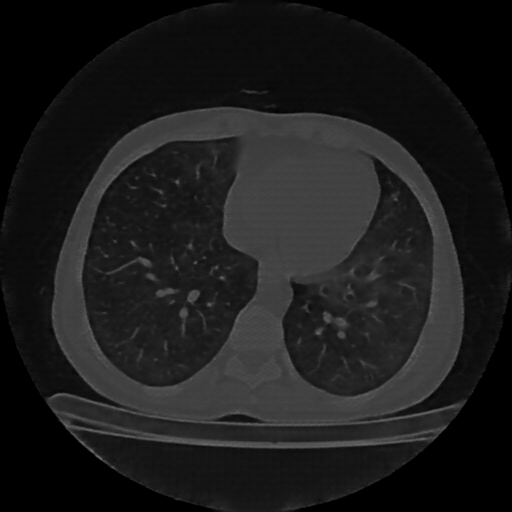

Targeted Slice 70 - Lung Window Analysis (Generated vs Real Venous)

0.527

Lung SSIM

164.1

Lung RMSE

121.4

Lung MAE

Average Lung Window Metrics Across All Slices (112 slices) - Generated vs Real Venous

0.579

Lung SSIM (Avg)

137.7

Lung RMSE (Avg)

95.0

Lung MAE (Avg)

Original NATIVE CT scan (input)

No window - Raw intensity values

Lung window (WL -600, WW 1500 β†’ Low βˆ’1350, High +150)